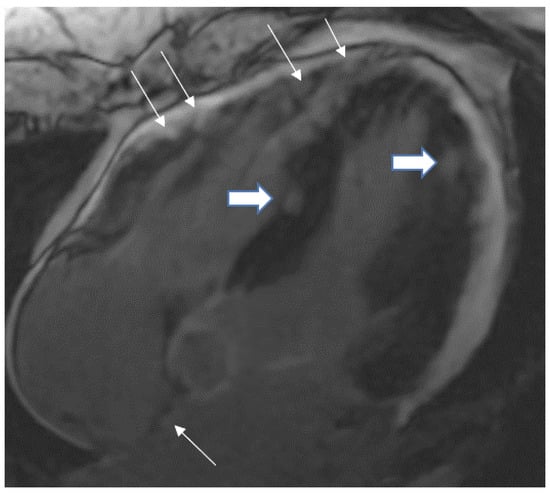

Figure 3.

A 35-year-old male with a recent history of treated tuberculous pericarditis for six months had CMR for ventricular tachycardia. 4 CH, late enhancement images, shows RV free wall (epicardial and transmural thin arrows), inferior septal (transmural- thick Arrow), lateral wall LV (transmural-thick arrow), and interatrial septum (thin arrow) enhancement.